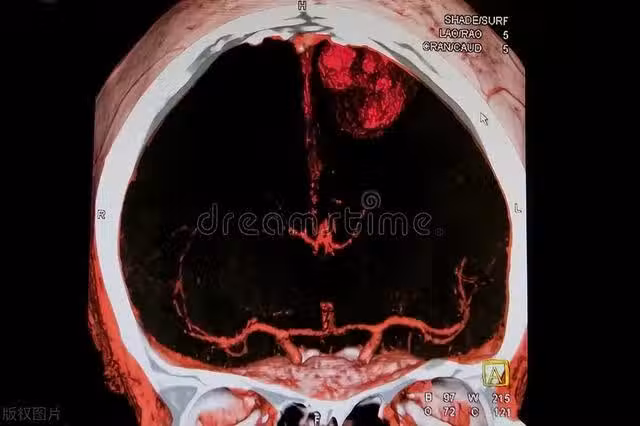

提醒:身體的3個異常,是腦中風發出的「紅色警告」,忽視不得

識別並及時響應中風的徵兆可能會挽救一個人的生命或避免長期的殘疾。無論您是否有中風的風險因素,都應該對這些「紅色警告」保持警惕。身體給出的信號不應被忽視。如有任何疑慮或出現上述症狀,請立即尋求醫療幫助。您的及時行動可能會使自己或他人得以生存。